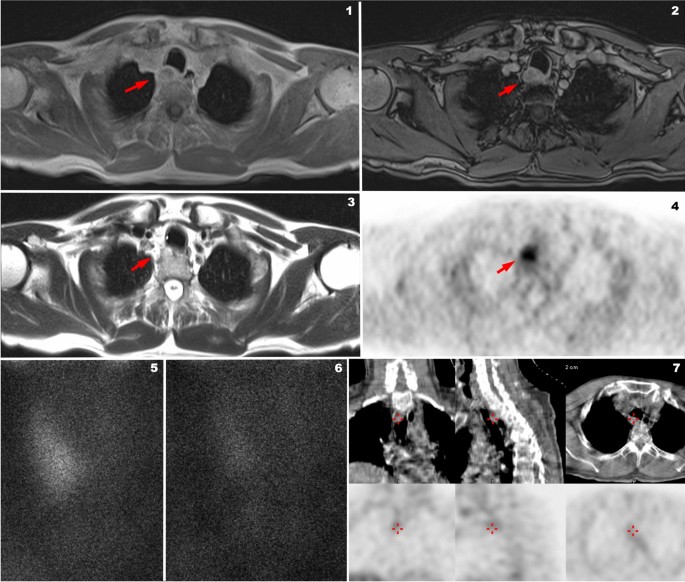

In the study by Kluijhout et al. [14], 10 patients were studied with FCH PET and MRI, and compared with the same patients examined using US and a dual-phase 99mTc-MIBI SPET/CT. While for PET/MRI the sensitivity was 90% and the positive predictive value (PPV) was 100%, MRI alone showed a sensitivity of 55.6% and a PPV of 83.3%. In Fig. 2 is reported a 65-year-old patient with persistent hyperparathyroidism after surgery who underwent FCH PET/MRI in our Department.

Example of positive 18F-FCH PET/MRI (Biograph mMR, Siemens Germany) and negative 99MTc-MIBI SPECT/CT (Infinia Hawkeye, GE Healthcare) performed at the University Hospital of Padova, Department of Medicine, Unit of Nuclear Medicine in a patient with hyperparathyroidism after left thyroidectomy (during a surgical procedure of left parathyroidectomy). MR axial Caipirinha in-phase (1) and MR axial Caipirinha out of-phase (2) demonstrating an ovoidal mass (red arrows) partially liquid at axial T2-Haste (3) with a very high posterior, paratracheal uptake of 18F-FCH PET/MR (4, red arrow). 99MTc-MIBI early after injection (5) and late after injection (6) phases of the same patient demonstrating no significant late retention of MIBI in the area revealed by 18F-FCH PET/MRI. SPET/CT of the same patient revealed only faint uptake (7: red cross) of MIBI in the paratracheal area revealed by 18F-FCH PET comparable to the background